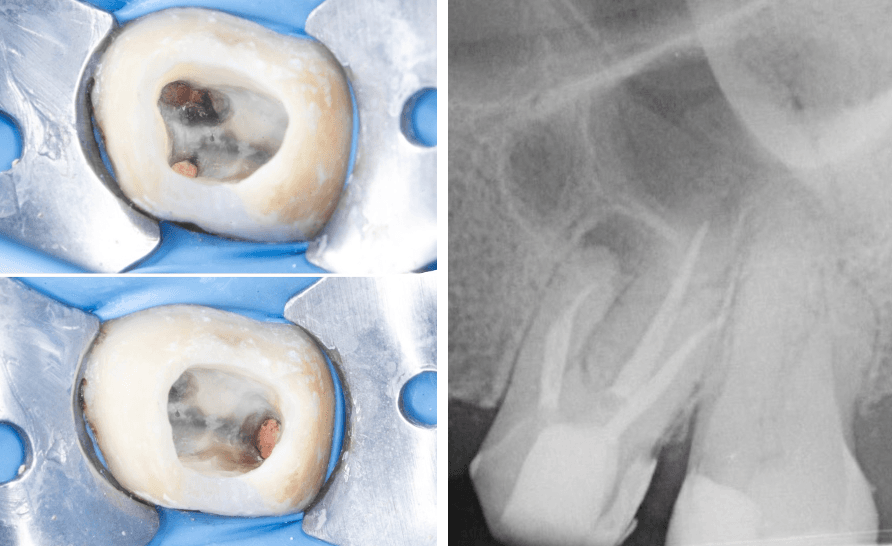

Apikal üçlüdeki alet ED 87 numaralı ultrasonik uç ile enerji verilerek çıkartıldı. Basamak atlanarak radyografik olarak doğrulandı. (Şekil 6a-6b)

Şekil 6a. Kontrol

Şekil 6b Basamak atlandıktan sonra gutta prova

Her eğeleme sonrası 2 ml %2,5 NaOCl ile irrigasyon yapıldı. Sonrasında kanal içi medikament yerleştirilerek geçici olarak kapatıldı. İkinci seansta hastanın asemptomatik klinik tablo sergilemesi üzerine preperasyon tamamlandı, güta-perka ve Adseal kanal dolgu patı ile soğuk lateral kondensasyon tekniği kullanılarak kanallar dolduruldu (Şekil 7).

(Şekil 7) 2025 Mayıs İntra-op ve Post-op görüntüler